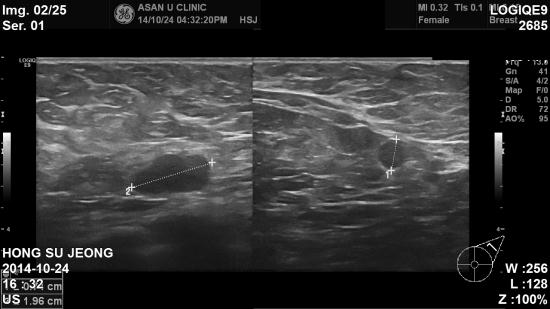

초음파상 좌측 11시방향 0.82cm, 10시 방향 3.34cm 미

좌측 겨드랑이 림프절 비대소견으로

조직검사 및 세침검사 시행 하여

침윤성 유관암 및 겨드랑이 전이로 진단 되었습니다.